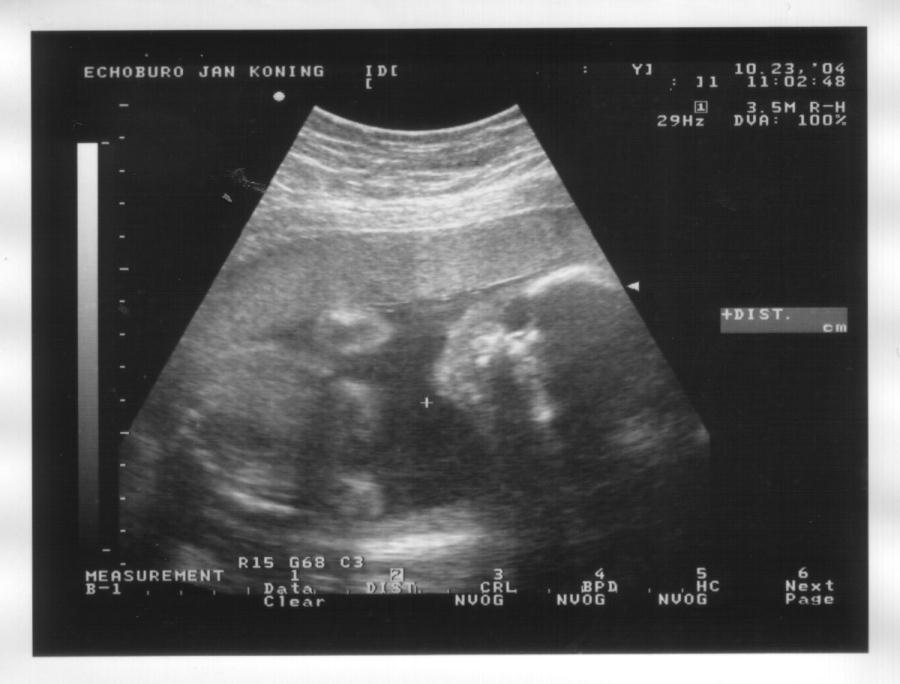

23 oktober 2004

Zijaanzicht hoofd, handje bij het gezicht en oog, bovenste helft borst, opgetrokken knietjes